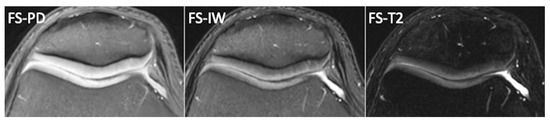

2.5. T2-Mapping

- Mosher, T.J.; Dardzinski, B.J.; Smith, M.B. Human Articular Cartilage: Influence of Aging and Early Symptomatic Degeneration on the Spatial Variation of T2—Preliminary Findings at 3 T. Radiology 2000, 214, 259–266. [Google Scholar] [CrossRef] [PubMed]

- Nischal, N.; Iyengar, K.P.; Herlekar, D.; Botchu, R. Imaging of Cartilage and Chondral Defects: An Overview. Life 2023, 13, 363. [Google Scholar] [CrossRef]

| T2-mapping | T2*, UTE-T2*, T2w SE, FSE, Multi Echo SE, Turbo Gradient SE, DESS Cartilage hydratation, Cartilage, Water | High reproducibility. T2* and UTE sequences allow a better visualization of deep cartilage and osteochondral junction. Predictive for OA in areas with much compression loading. No contrast administration. | Susceptible of magic angle artifact and magnetic field inhomogeneity. |